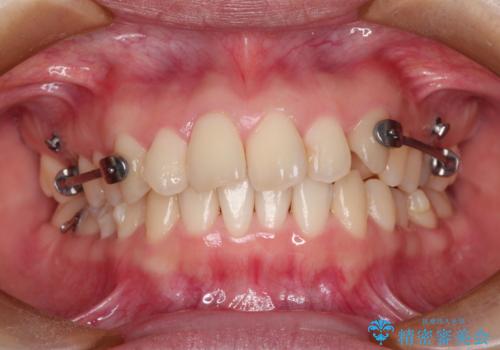

- 出っ歯の改善を希望され来院された患者様です。

初診時の歯並びの状態としては、上下とも前歯部の中等度のがたつきがあり、その他に奥歯の噛み合わせのズレや、口元の突出感も認められました。

抜歯矯正の可能性もご提案しましたが、ご本人の強い希望もあり、抜歯なし/インビザラインによるマウスピース矯正にて治療を行いました。